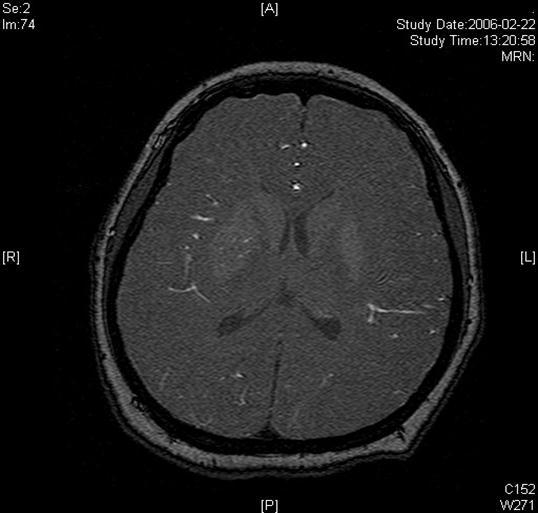

A twenty-nine-year-old female was admitted in Feb, 2006 because of episodic left limb numbness and weakness for half a year. The duration of the episode lasted for a few minutes, seldom over ten minutes. There was an attack every several days. She denied special medical history. She did not live in the pandemic area of Leptospirosis. Her blood pressure was 110/65mmHg and body weight was 51 kilograms. Physical examination found no abnormality. Magnetic resonance angiogram (MRA) (Feb 22) showed severe stenosis in the M1 segment of right MCA. In the source images of MRA, an oval area of abnormal signal in the right basal ganglion was found (Figure 1). Blood routines, coagulation tests, blood biochemistry tests, and C-reactive protein level were normal. The anti-nuclear antibody (ANA), anti-extractable nuclear antigen (ENA) antibodies, and anti-neutrophil cytoplasmic antibodies (ANCA) were negative. Serologic test for Syphilis was negative. Blood sedimentation rate (ESR) was 20 mm/h, and the level of anti-streptolysin O microtitration test (ASO) was 395 IU/ml (0-200 IU/ml). Digital subtraction angiography (DSA) detected severe stenosis (95%) in M1 segment of the right MCA, and the distal blood flow was compromised (Figure 2). The patient was given aspirin 100mg/d, clopidogrel 75mg/d and atorvastatin 20mg/d since Feb 26. Due to the finding of high ASO level, she was given penicillin (4 million IU, bid) for a week. Because of disagreement between the consulting physician and the interventional radiologist, her angioplasty and stenting was delayed till Mar 21 on her request. During the waiting time, her attacks did not reduce. Before the operation, besides the combination of aspirin and clopidogrel, subcutaneous low molecular weight heparin (LMWH) (5000U, q12h) was given for 5 days. After a complete diagnostic evaluation of the blood vessels with DSA, stenting was performed with a stainless steel stent 2.75 mm in diameter by 1.5 cm in length (PC, Abott Company) at the presure of 7 atm. No compromise of perforating branches was found and residual stenosis was less than ten percent on angiography (Figure 2).

Figure 1.Lesion in the right basal ganglia displayed in the source image of MRA